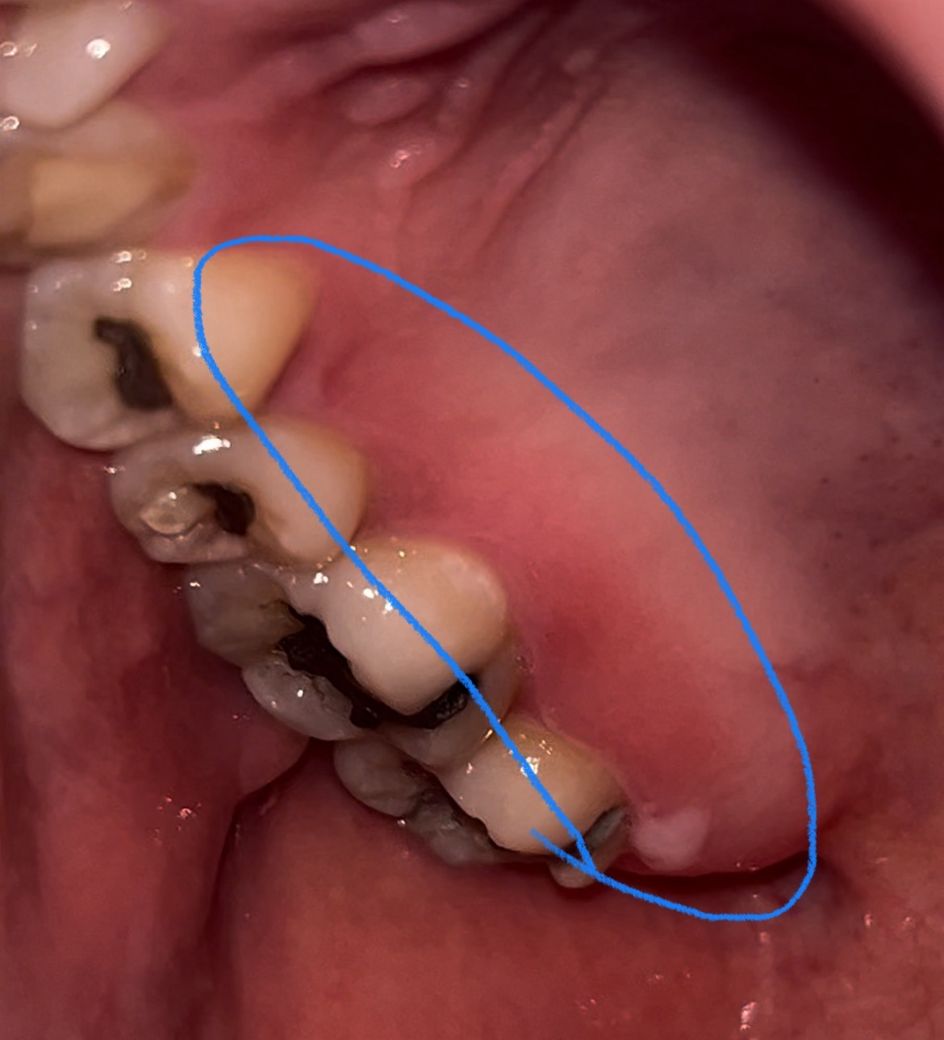

이거 그냥 잇몸 염증이겠죠? 성병같은거 아니죠?

방금 어쩌다 알게된건데 윗 어금니쪽 ㅇ안쪽 잇몸이 아픈건 아닌데 껍질까진거같은 느낌 처럼 불편한거같고 잇몸이 그부분만 말랑말랑 물집 잡힌거처럼 느껴지고 완전 안쪽 어금니쪽엔 하얀게 뭔가 있네요

기본 구내염이나 일반 잇몸염증처럼 자연치유가 되거나 약만 먹으면 되는거면 모를까 혹시 헤르페스나 hPV같은거일까봐 걱정되네요 얼마전 STD 산부인과 가서 했는데 다 음성이긴 했는데 구강을 검사한건 아니니까ㅠㅠ

성병보다는 궤양성 치은염이 의심되긴 하지만 치과에서 검사를 받아보시는 편이 좋아보입니다.

사진으로 봤을 경우에는 잇몸의 염증으로 보입니다.

잇몸의 염증은 치아주변의 치석 등으로 인해서 생길수 있습니다 이런경우 잇몸치료등으로 통해서 잇몸의 염증을 줄일수 있습니다.